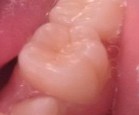

Bệnh nhân: Trần Gia K. 8 tuổi, nam, mã BA 8233/17

Sau ba tháng. ICDAS:2; Di: 21 | Sau sáu tháng. ICDAS:1; Di: 17 | Sau 18 tháng. ICDAS:0; Di: 05 |